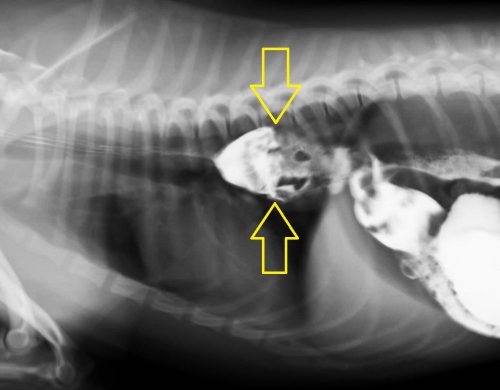

下が造影検査によって明らかになった胸部食道の異物の例です。上2枚の写真はリンゴ、下2枚は牛皮ガムが異物となっています。犬のおやつ類などは硬く、見た目に明らかな異物であっても撮影条件によっては意外にレントゲン写真に写りにくいため、診断する上で難しさを生じます。